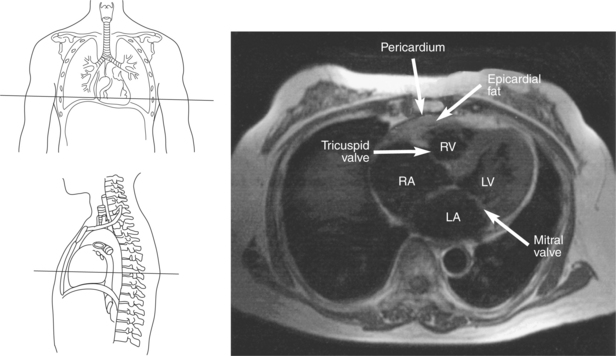

The heart is enclosed in a pericardial sac that surrounds the heart and the proximal portions of the great vessels entering and leaving the heart. The fibrous pericardium is attached to the central tendon of the diaphragm and is pierced by the inferior vena cava. The inner surface of the fibrous pericardium consists of a double-layered serous membrane termed the serous pericardium. The serous pericardial layers are the parietal layer that lines the inner surface of the fibrous pericardium and the visceral layer (epicardium) that covers the outer surface of the heart and the roots of the great vessels. Located between the two layers is a potential space (pericardial cavity) containing a thin film of serous fluid that acts as a lubricant to reduce friction to the tissues caused by heart movement. Located between the pericardium and the heart wall is a layer of epicardial fat that is typically more prominent near the venous inflow and arterial outflow of the heart (Figures 6.36 through 6.38).

The right atrium forms the right border of the heart and receives deoxygenated blood from the body via the superior and inferior venae cavae and from the coronary sinus and cardiac veins that drain the myocardium. A small muscular embryonic appendage, the right auricle, projects upward and toward the left from the right atrium, covering the root of the aorta (Figure 6.40). The right ventricle lies on the diaphragm and comprises the largest portion of the anterior surface of the heart. It receives deoxygenated blood from the right atrium and forces it into the pulmonary trunk for conveyance to the lungs. Projecting off the inferior surface of the ventricular walls are conical-shaped projections of cardiac muscle called papillary muscles that anchor the cusps of the tricuspid valve to the right ventricle (Figure 6.39). The left atrium lies posterior to the right atrium and is the most posterior surface of the heart. It also has an embryonic appendage, the left auricle, that projects to the left of the pulmonary trunk over the superior surface of the heart. The left atrium receives oxygenated blood directly from the lungs via the four pulmonary veins (two on each side). The left ventricle forms the apex, left border, and most of the inferior surface of the heart. It receives oxygenated blood from the left atrium and pumps it into the aorta for distribution throughout the systemic circuit. The myocardium of the left ventricle is normally three times thicker than that of the right ventricle, reflecting the force necessary to pump blood to the distant sites of the systemic circulation (Figures 6.41 through 6.52). Two papillary muscles project from the ventricular walls to anchor the bicuspid valve to the ventricle (Figures 6.39 and 6.47).

Four valves are located in the heart that function to maintain one-way directional blood flow throughout the heart. The valves can be divided into two groups: atrioventricular and semilunar (Figure 6.51).

The two atrioventricular valves are found at the entrances to both ventricles and function to prevent backflow of blood between the atria and ventricles during ventricular contraction. These valves have leaflets that are attached to the papillary muscles by thin cords of fibrous tissue called chordae tendineae. The right atrioventricular valve, with three leaflets, is called the tricuspid valve, and the left atrioventricular valve, with two leaflets, is called the bicuspid (mitral) valve (Figures 6.39, 6.43, 6.44, 6.47, and 6.48).